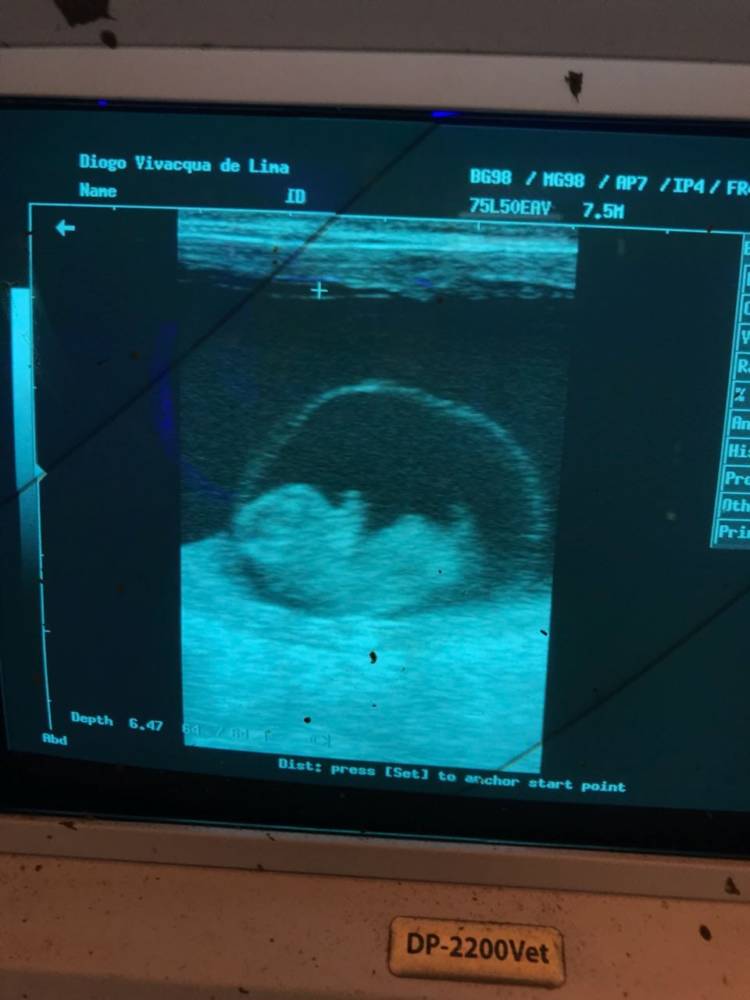

A ultrassonografia é uma ferramenta que possibilita o médico veterinário ser mais conclusivo nos exames e não deixa sequelas para o gado ou para o feto, no caso das vacas ou novilhas gestantes.

Para se fazer esse diagnóstico de gestação deve-se colocar a vaca ou novilha no tronco de contenção e o médico veterinário pode fazer o diagnóstico de duas formas: por palpação simples ou pela técnica da ultrassonografia. A palpação manual foi a técnica feita durante muitos anos, porém vem diminuindo, devido a maior precisão do diagnóstico com o ultrassom. No meio da década de 90 começou a utilização do ultrassom para melhorar controle do manejo reprodutivo do rebanho, pois com o uso dessa nova ferramenta pode-se fazer:

- Diagnóstico precoce (com 30 dias) e acompanhamento da gestação;